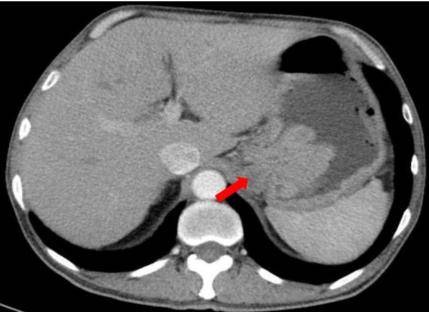

腹盆CT:左肾上部肾实质内可见肿块影,大小约6.6*6.9cm,其内密度不均,与周围肾组织分界不清,增强扫描呈不均匀性强化,考虑肾癌可能。胃体底部小弯侧壁局限性增厚,形成肿块,最大截面大小约5.7*7.6cm,增强扫描强化较均匀,累及浆膜面,肝胃间隙内周围少量肿大淋巴结,大者约2.7*1.9cm,考虑胃癌可能。

PET/CT:贲门部、胃底部及胃体部胃壁增厚、局部软组织密度肿物形成,葡萄糖代谢增高,考虑恶性可能性大(胃癌?)。肝胃之间多发葡萄糖代谢增高淋巴结,考虑转移可能大。左肾上极混杂密度肿物,内伴钙化及坏死,葡萄糖代谢增高,考虑恶性可能性大(肾癌?)。

疗效评估:复查影像学显示贲门胃小弯侧肿瘤、肝胃间隙转移淋巴结及左肾占位均较前缩小。